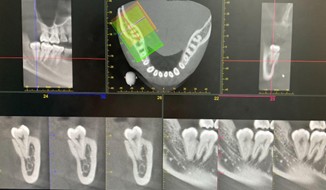

高精細な3D画像が撮影可能な『歯科用CT』

副鼻腔から歯根の形態、顎関節まで詳細に評価でき、幅広い診断・治療に対応可能です。

CT画像を活用した治療

インプラント治療

骨の厚みや密度を正確に把握し、安全な埋入計画。

埋入シミュレーション

口腔内スキャナーで採得したデータとCT画像を融合させることで、インプラントの埋入位置・角度・深さを正確に誘導するマウスピース型の装置『サージカルガイド』を作製。

親知らずの抜歯

神経や血管の位置を正確に把握し、安全な抜歯計画

歯周病の精密検査

歯槽骨の吸収状態や歯根の状態、病変の確認

歯根嚢胞や腫瘍の診断

病変の正確な位置、広がり、周囲組織との関係を把握

歯内療法の精密検査

根管の形態や病変の詳細を把握

歯根破折の診断

あらゆる角度から破折線を確認